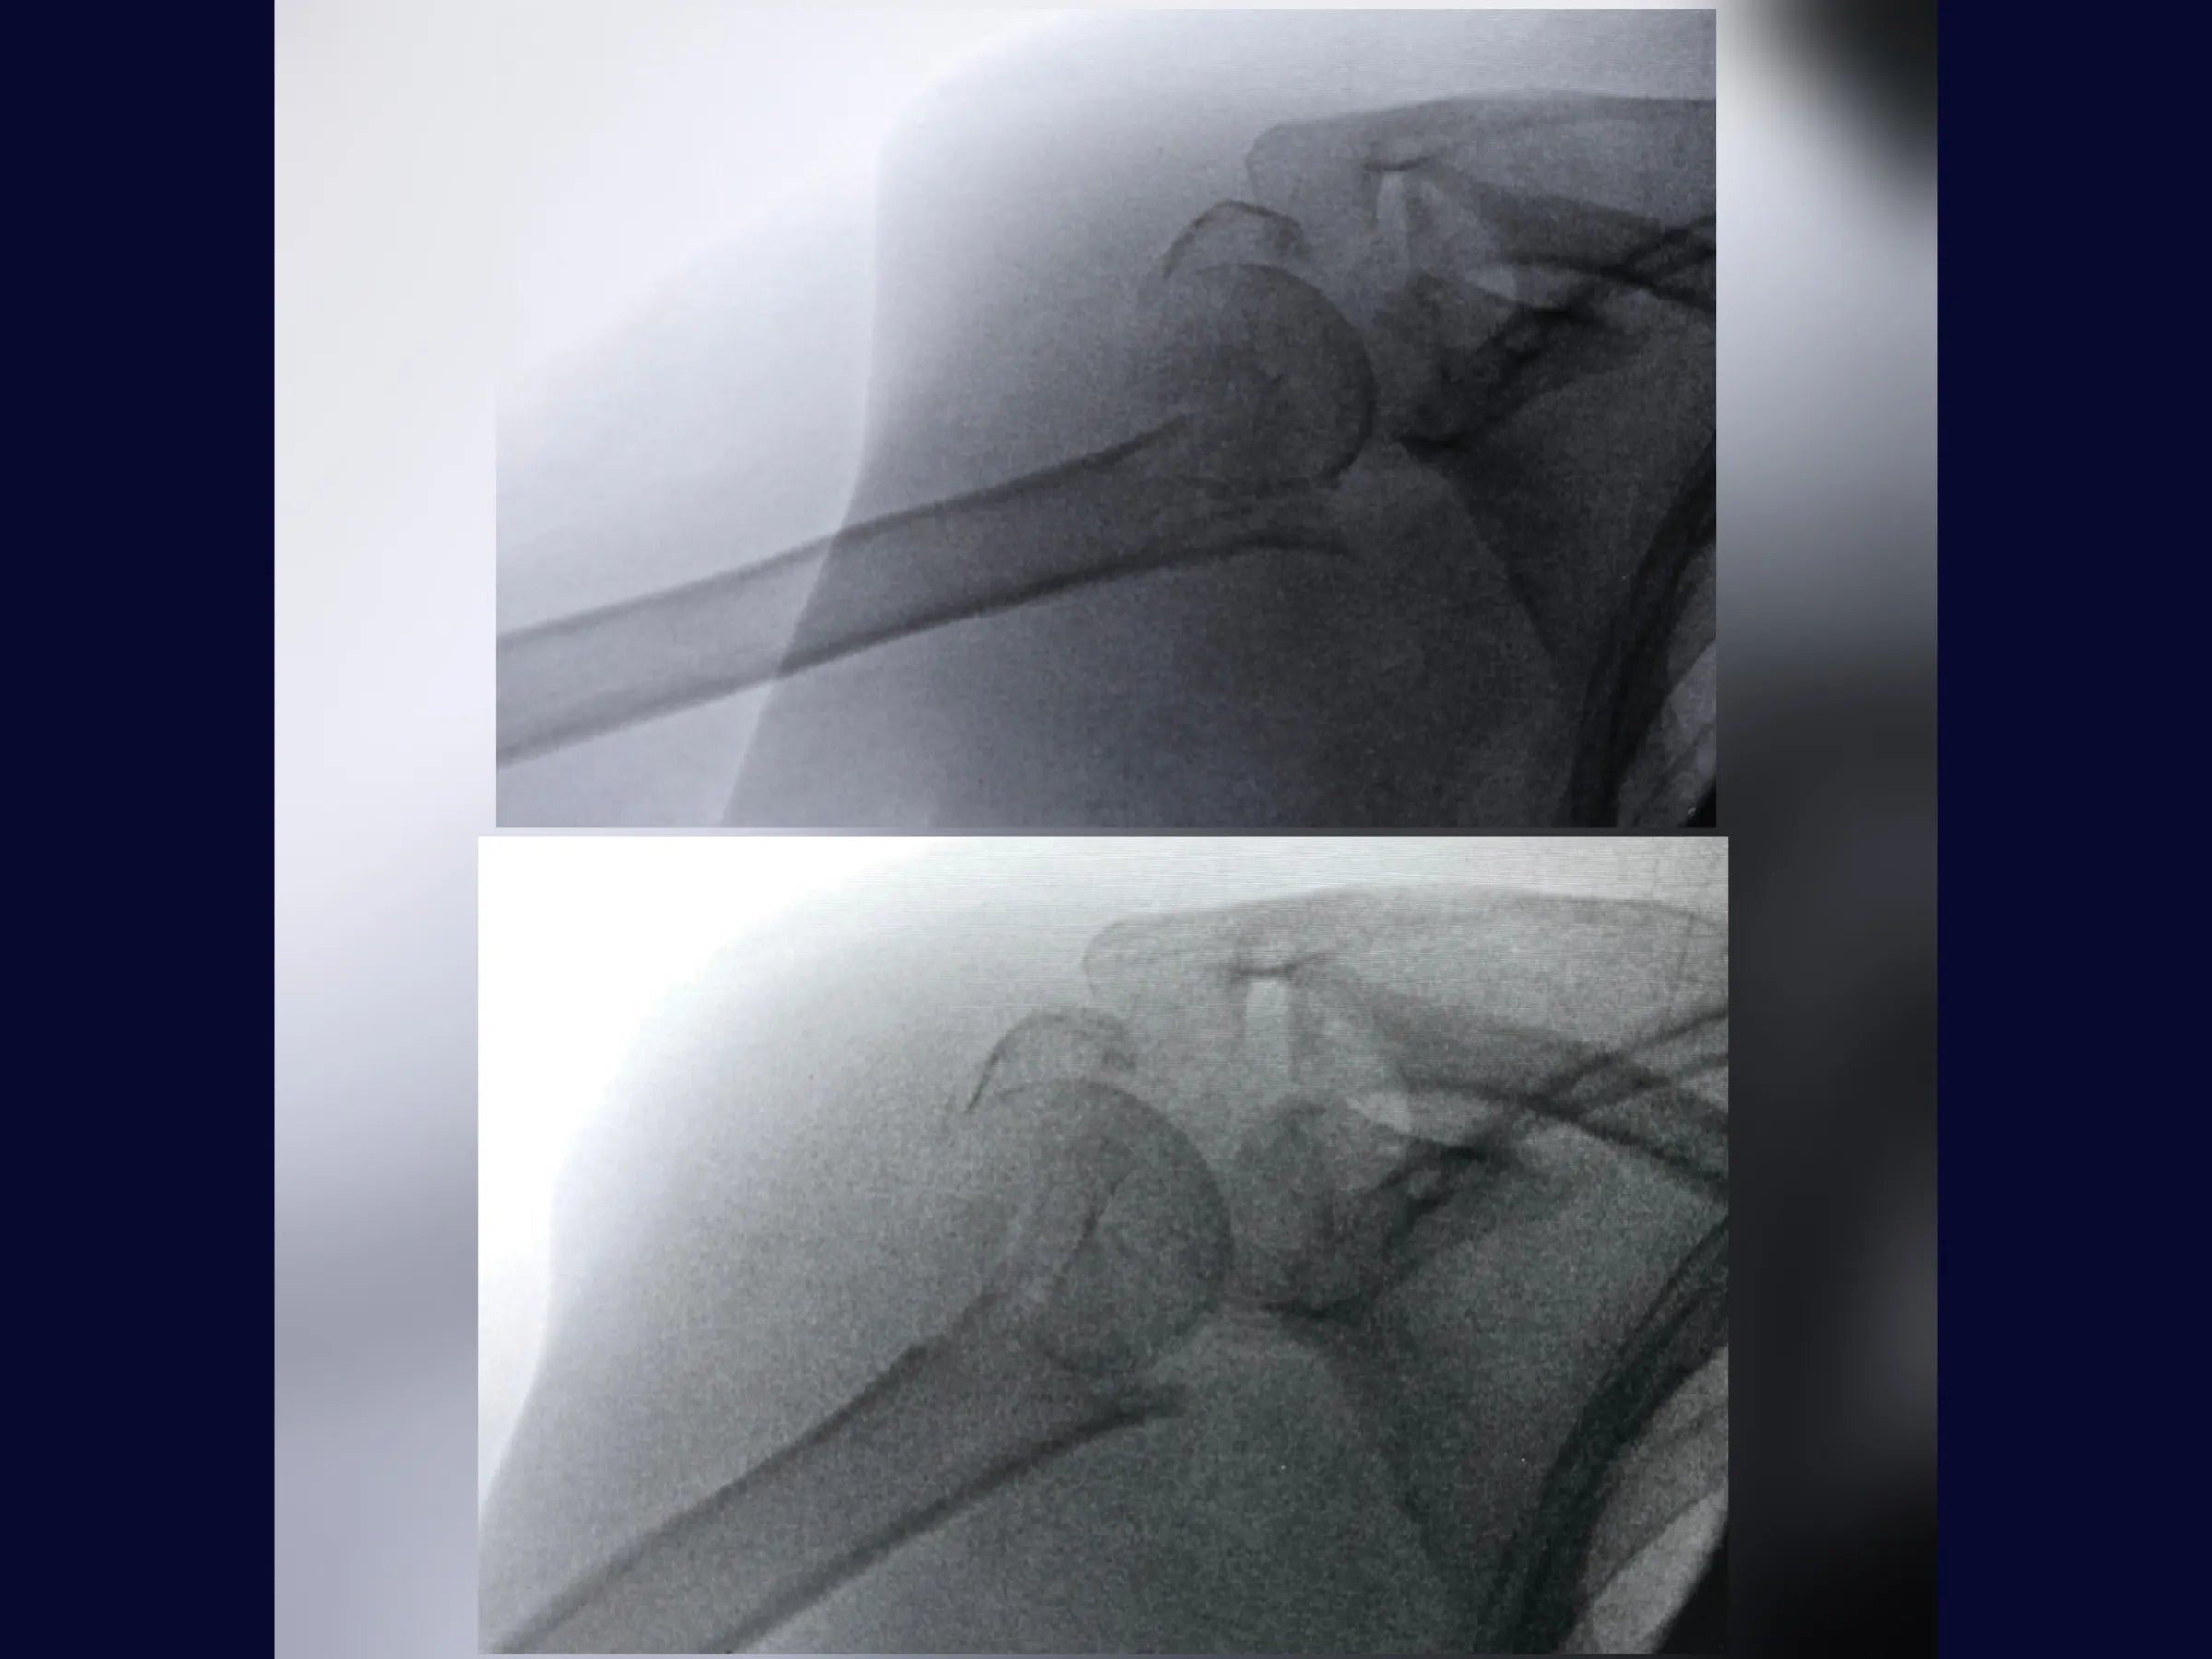

As fraturas complexas do úmero proximal, especialmente em quatro partes com impacto em valgo, exigem domínio técnico para restauração da anatomia e função.

Este treinamento apresenta, passo a passo, a reconstrução do úmero proximal por via deltopeitoral, com ênfase na redução anatômica das tuberosidades e fixação estável com placa bloqueada, demonstrada sob perspectiva cirúrgica detalhada.

- Controle Radiográfico e Ajustes Finais: Correção de cisalhamento e simetria com reposicionamento de parafusos.